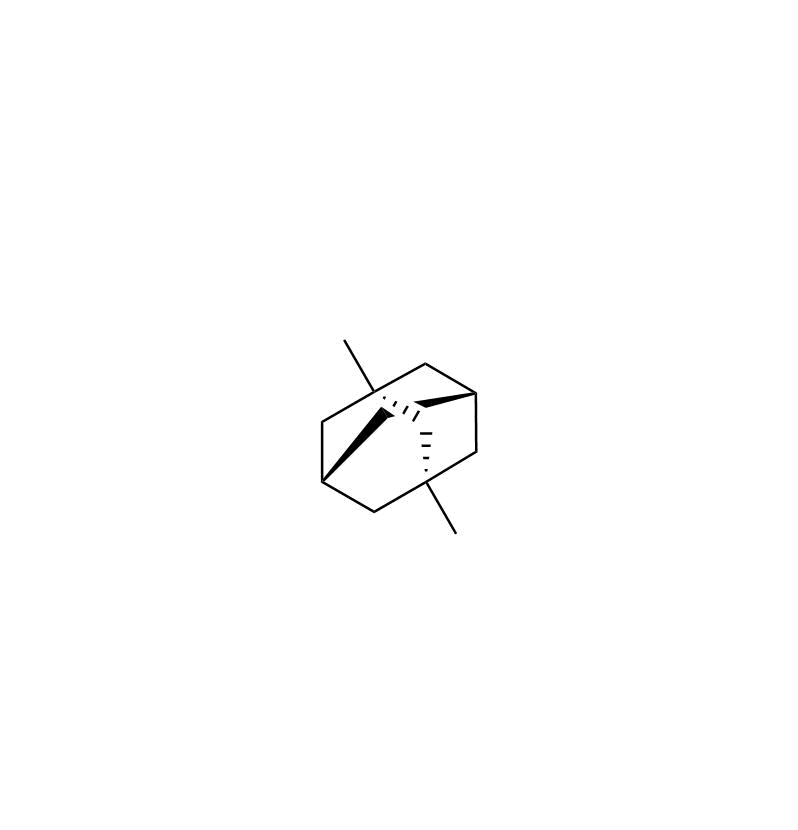

| CAS NO | 702-79-4 |

| Mol.F | C12H20 |

| Mol.Wt | 164.3 |

| Chemical name | (1r, 3r, 5s, 7s)-1, 3-dimethyladamantane |